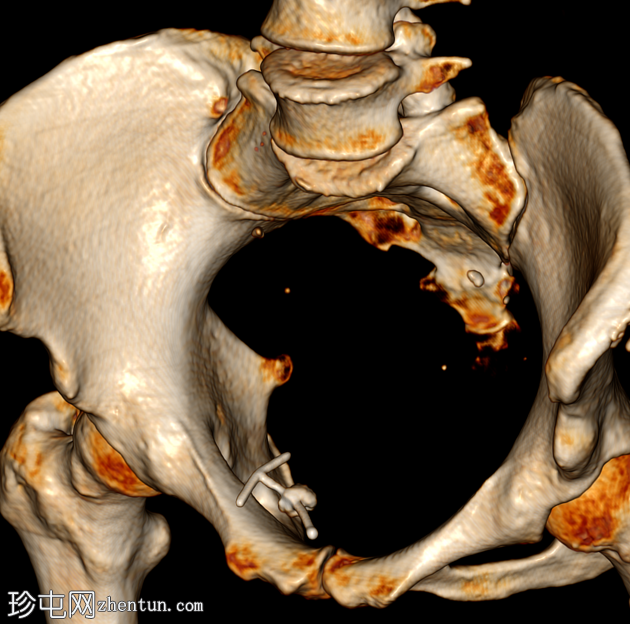

三维重建

移位的宫内节育器(IUD)长臂两次穿透增厚的膀胱前壁。中部位于膀胱内,周围有结石和气体。

宫内节育器子宫穿孔是一种严重的并发症,可损伤受累器官并引起感染。本病例较为罕见,宫内节育器弯曲的长臂两次穿透膀胱前壁,而T形顶端缠绕在膀胱前壁内。另一个并发症是膀胱内结石的形成,推测是由于继发感染和宫内节育器作为结石形成中心所致。